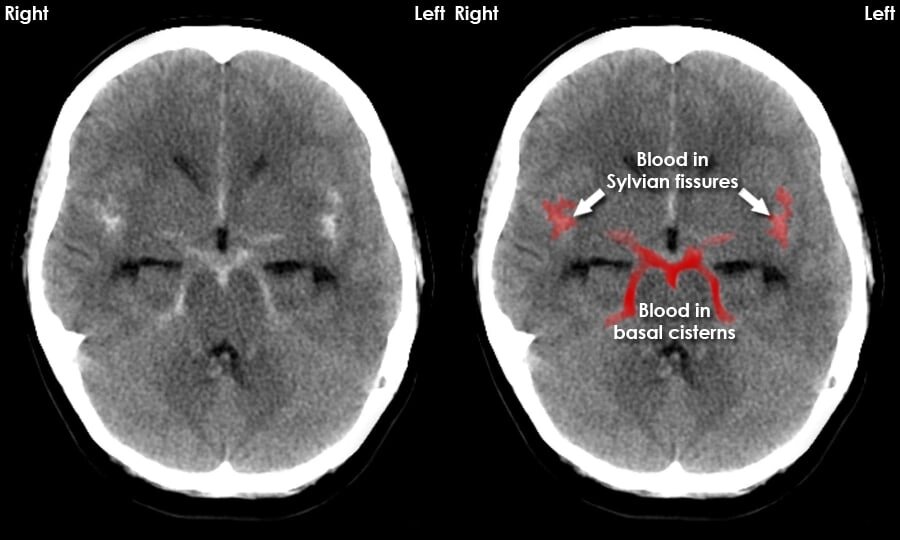

Нетипичные варианты субарахноидального кровоизлияния - это когда кровь вытекает в пространство между паутинкой и мягкими оболочками мозга не из аневризмы, а из-за других причин, таких как сосудистые дефекты или травма головы. Это делает диагностику и лечение таких случаев сложными и требующими специализированного медицинского вмешательства.

Цефалгический синдром - одно из самых загадочных и неизученных заболеваний, которое может возникнуть в результате нетипичных вариантов субарахноидального кровоизлияния. Это состояние сопровождается острыми и интенсивными головными болями, которые могут привести к серьезным последствиям, если не обратить на них внимание. Нетипичные варианты субарахноидального кровоизлияния - это когда кровь вытекает в пространство между паутинкой и мягкими оболочками мозга не из аневризмы, а из-за других причин, таких как сосудистые дефекты или травма головы. Это делает диагностику и лечение таких случаев сложными и требующими специализированного медицинского вмешательства. Особенность цефалгического синдрома при нетипичных вариантах субарахноидального кровоизлияния заключается в его интенсивности и продолжительности. Головная боль может быть такой силы, что пациент не в состоянии выполнять привычные повседневные задачи и даже проходить через обычные ритуалы, такие как умывание или одевание. Она мо